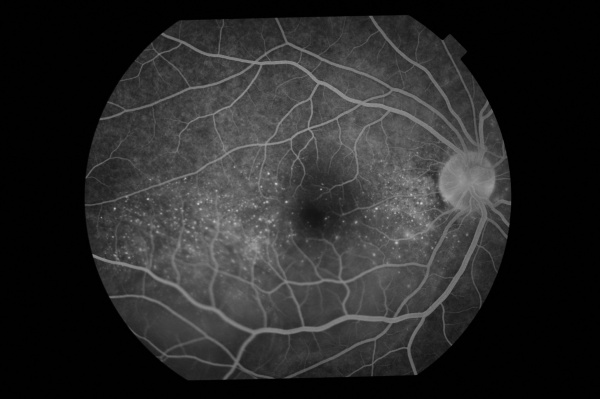

Fundus Fluorescein Angiography (FFA)

During the acute stage of the disease, we find an early irregular focal or patchy fluorescence of the choroidal circulation. There exist various pinpoint areas of leakage at the level of the retinal pigment epithelium. In the later phases, the localized hyperfluorescent spots increase in size, coalesce, and expand into the subretinal space in areas of serous detachment leading to a large area of leakage. The optic disc can demonstrate blurred fluorescent margins accompanied by late leakage.

In the chronic stage of the disease, the presence of diffuse scattered pigmentary changes with markedly pigmented areas adjoining hypopigmented ones (“moth-eaten” appearance) are the hallmark. [11][15]

Soon-Phaik Chee and colleagues report findings in their retrospective study that indicate the importance of early pinpoint peripapillary hyperfluorescence as a prognostic factor in VKH. The absence of this sign suggests that the disease is no longer in its early stages, indicating the need for more aggressive and prolonged treatment to prevent future recurrences. [16]